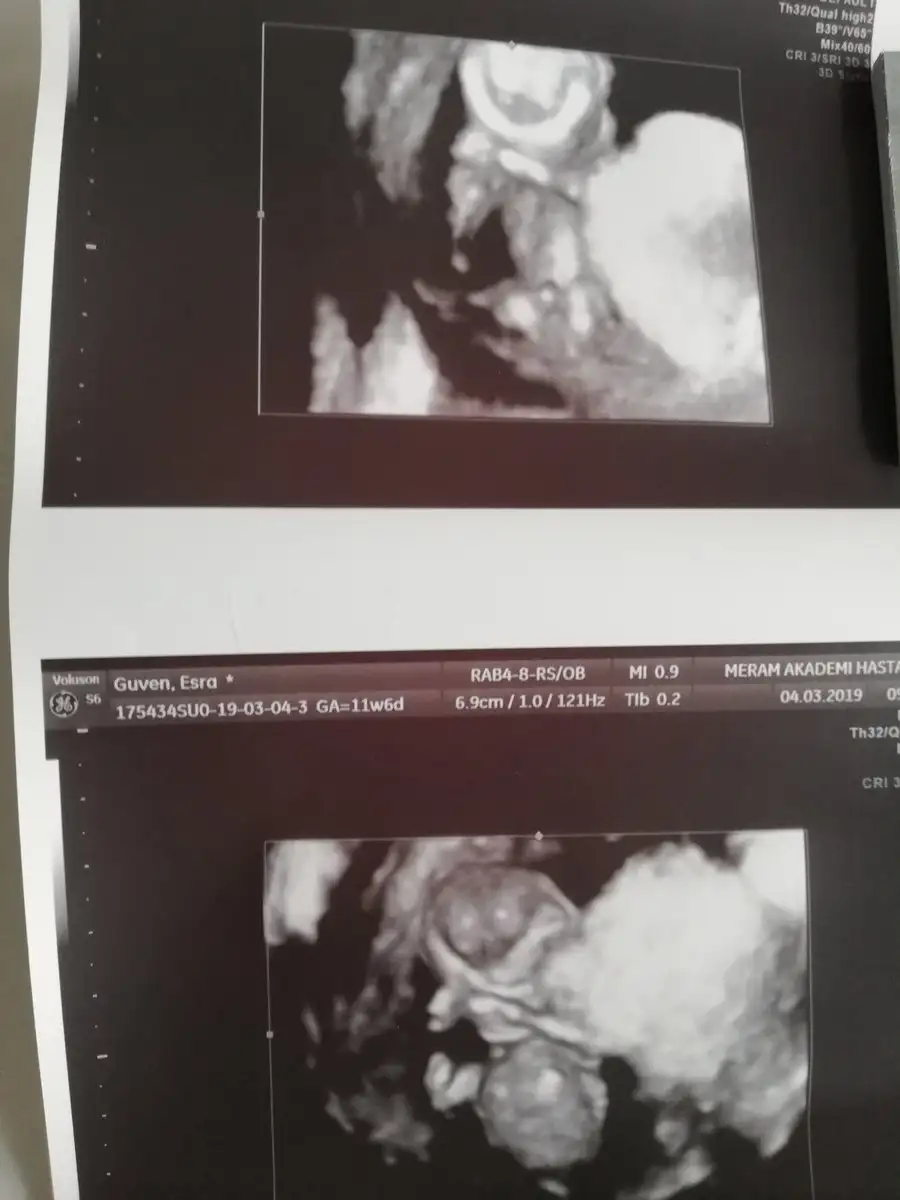

Teyzeleri geldik biiizzz. %100 erkek dedi, ense kalınlığı 1.4 cm cıktı. 5 gün önden gidiyormuş herşey yolunda dedi doktor şükür. Darısı ogrenmeyenlerin başına

Ooh gözün aydın hadi oğlan anası oldun demek :))) yalnız enseleri bile aynı bizimkilerin benim de 1.4 tü yavrumun :) bakalım benimkinin cinsiyeti ne olacak. Bende yüksek ihtimal erkek diye düşünüyorum ama bakalım :) gözün aydın Rabbim sağlıklı kucağına almayi da göstersin